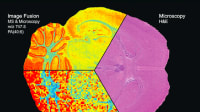

A new microscope system can image living tissue in real time and in molecular detail, without any chemicals or dyes. The system uses precisely tailored pulses of light to simultaneously image with multiple wavelengths. This enables the researchers to study concurrent processes within cells and tissue and could give cancer researchers a new tool for tracking tumor progression and physicians new technology for tissue pathology and diagnostics.

The technique, called simultaneous label-free autofluorescence multi-harmonic microscopy, differs from standard tissue pathology in several ways. First, it is used on living tissue, even inside a living being, giving it the potential to be used for clinical diagnosis or to guide surgery in the operating room. Second, it uses no dyes or chemicals, only light. Standard procedure involves removing a tissue sample and adding chemical stains — which can be a lengthy process — and the chemicals can disrupt the cells.